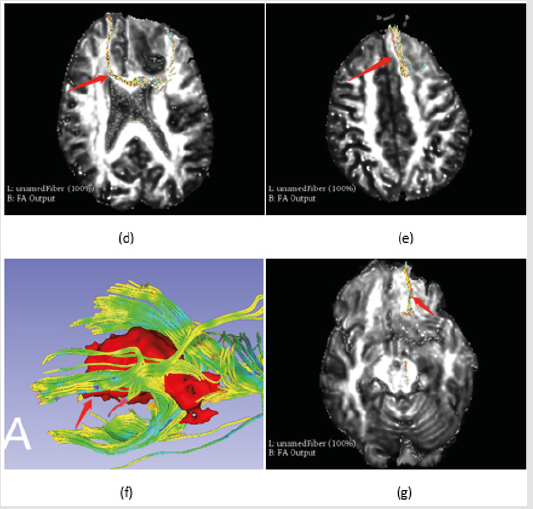

The fibers could be identified according brain atlas under brain tissue visualized. Meanwhile, VTK (virtual tool kit) models of fibers were exported and re-imported into slicer to find the position of the fiber in FA images (Figure 5 demonstrates).

Fibers Identification

Identifying the fibers is a key step to avoid dysfunction and improve the survival ratio after operation [6]. Brain atlas is always used to identify the fibers as Figure 5a-5c shows [7]. But it could only give a raw information about the fiber, as to identify the fiber in detail, the 2D projection of 3D model was approached in this paper. Fibers had been saved as vtk models and reimported into slicer, then, the fibers were displayed in Figure 5d-5g. 3D slicer 4.8.1 supports a key role in tumor and fibers visualization and identification. The diffusion module is very useful for displaying the fibers diffuse tensor imaging (DTI) via fiducial and label in tractography seeding tool kit.

Figure 5a: Fibers identification,

a) is the white matter of brain (download from website),

b) is the fibers in corpus callosum which was disrupted by the tumor, and

c) is the arcuate fibers between superior frontal gyrus and inferior frontal gyrus,

Figure 5b: Fibers identification,

d) and

e) are the VTK models which were displayed in transverse section respectively.

f) and

g) are the lower part fibers of corpus callosum from bottom aspect of the tumor.